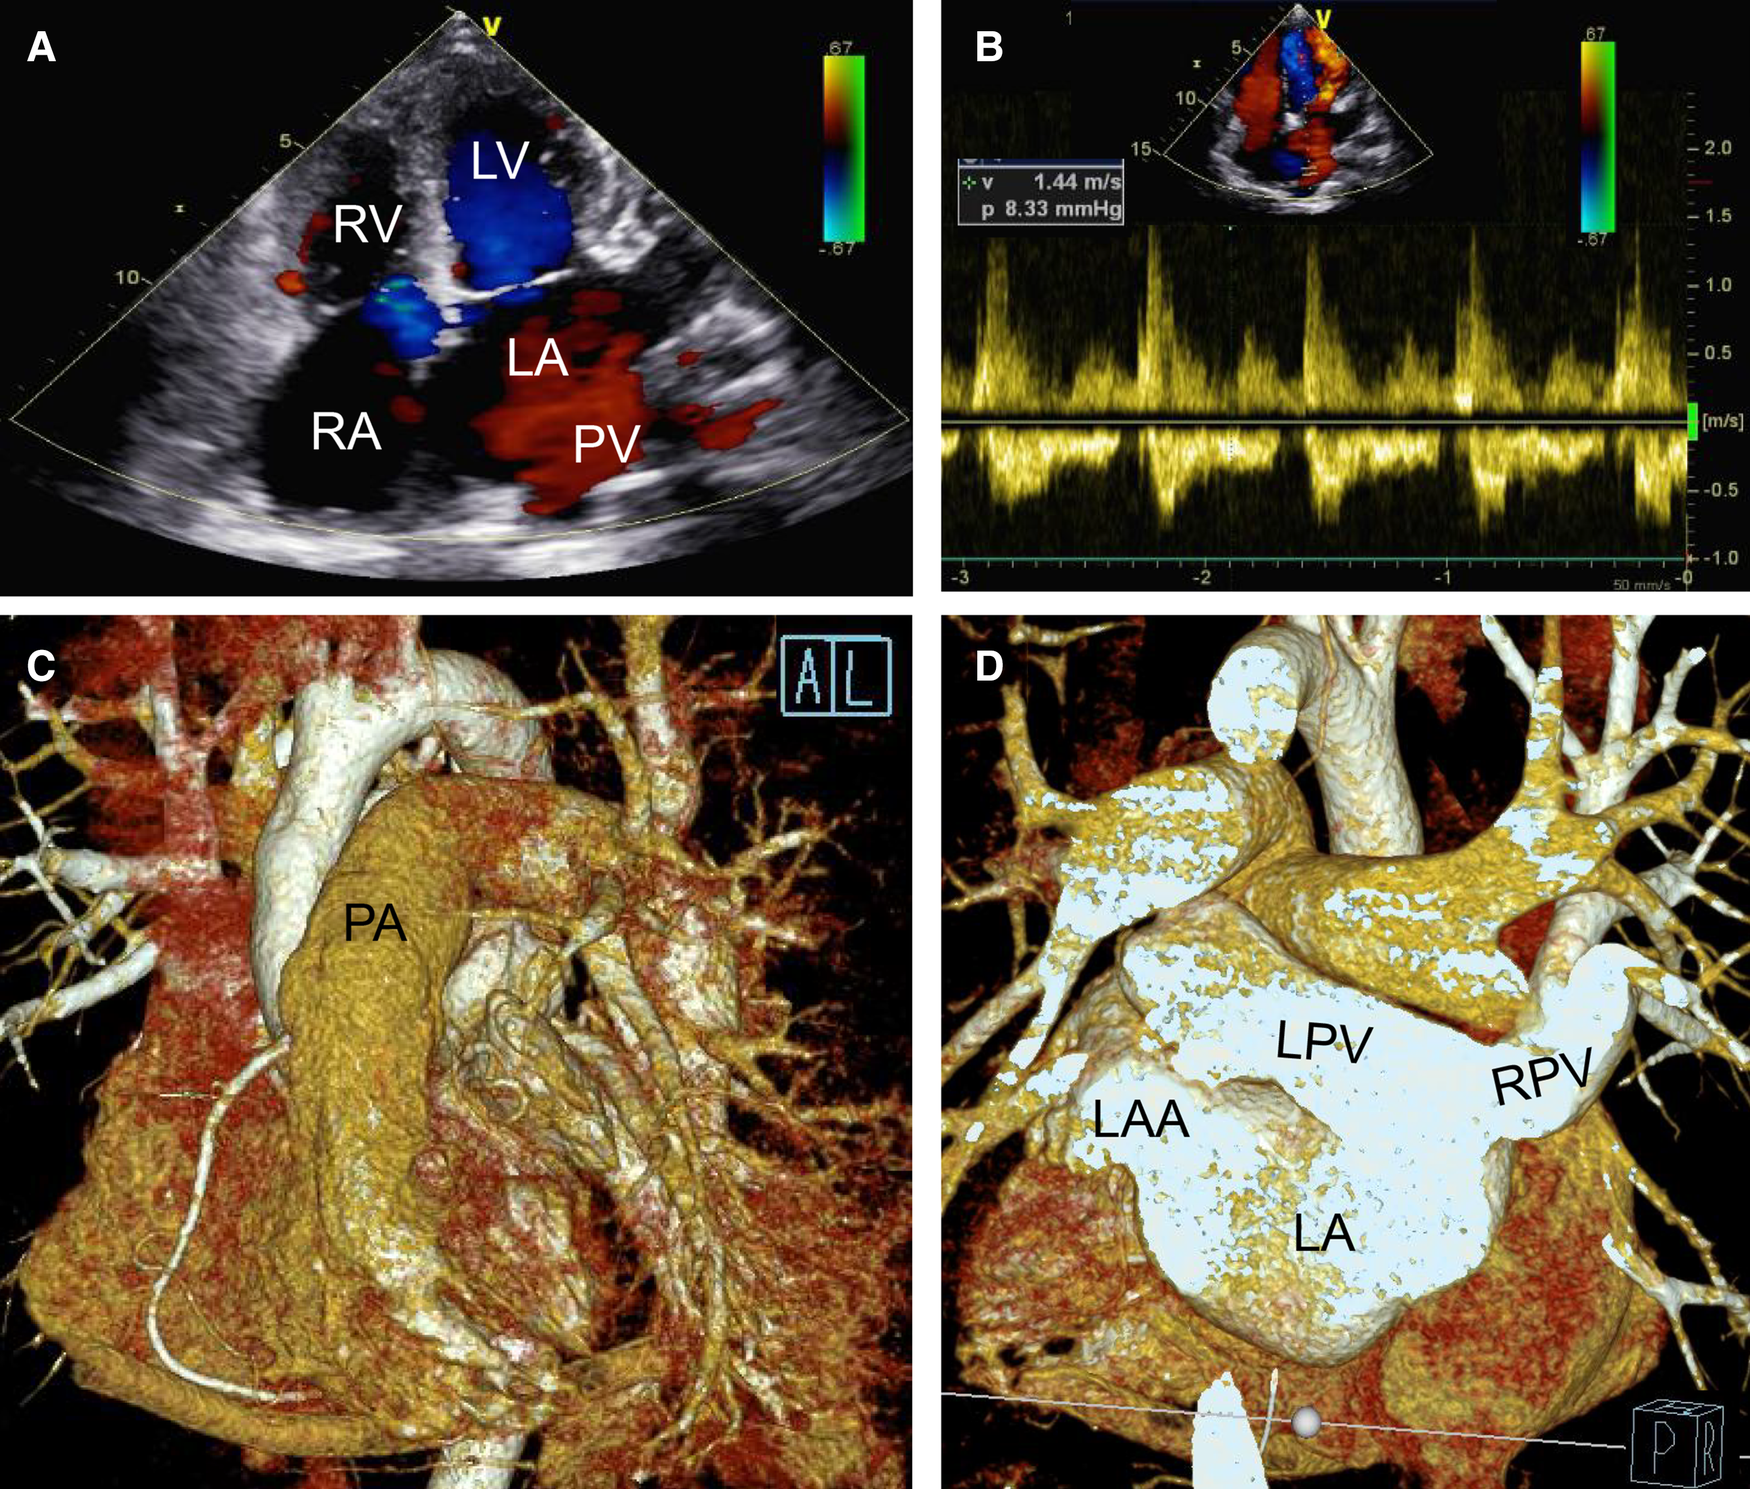

During the operation and after completely closing the ASD (II), we detected no pulmonary vein obstruction. Likewise, the left ventricle functioned well without mitral or aortic regurgitation (as seen on transesophageal echocardiography). Postoperative transthoracic echocardiography (Figures 4A,B), cardiac CTA, and a three-dimensional reconstructed figure (Figures 4C,D) showed that the surgical correction was satisfactory with entire pulmonary veins directly connected to the LA. The time consumption of CPB, aortic cross-clamp, mechanical ventilation, and post-surgery ICU stay were 139 min, 81 min, 4 days, and 30 days, respectively. The patient recovered well and was discharged without complications. The ECG at discharge indicated a significant atrial flutter and a right bundle branch block same as pre-operatively (Supplementary Figure S1B). There were no postoperative oral drugs used to eliminate pulmonary vascular resistance. Transthoracic echocardiography half-year, 1-year and 2-years post-surgery showed that the deformity correction was satisfactory without any anastomotic obstruction or residual shunt.

Figure 4

Postoperative transthoracic echocardiography (A,B) and cardiac CTA with three dimensional reconstruction figure (C,D) showing that the deformity correction was satisfactory without residual shunt (A) and pulmonary veinous obstruction (B) but with left and right pulmonary veins connected to the left atrium directly (C,D). LA, left atrium; LAA, left atrium; LPV, left pulmonary vein; LV, left atrial appendage; PA, pumonary artery; PV, pumonary vein; RA, right atrium; RPV, right pulmonary vein; RV, right ventricle.